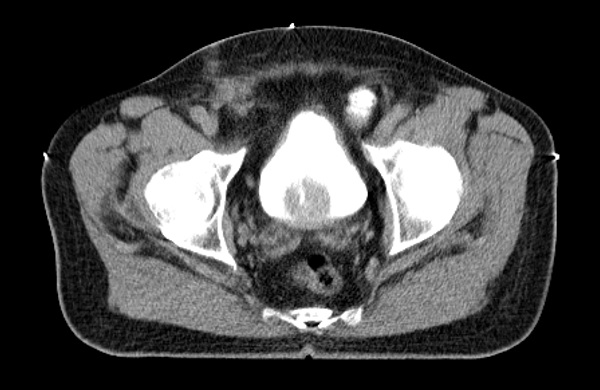

Radiotherapy planning software is responsible for generating contours for protection of risk organs and contours for tumor areas. To exemplify this process, below are the contours and radiations for you to interact with! Change the position of the slide (green circle) and check the outlines and rays (radiation) generated with SIPRAD for a radiotherapy treatment.

Generation of protective contours of risk organs and tumor areas.